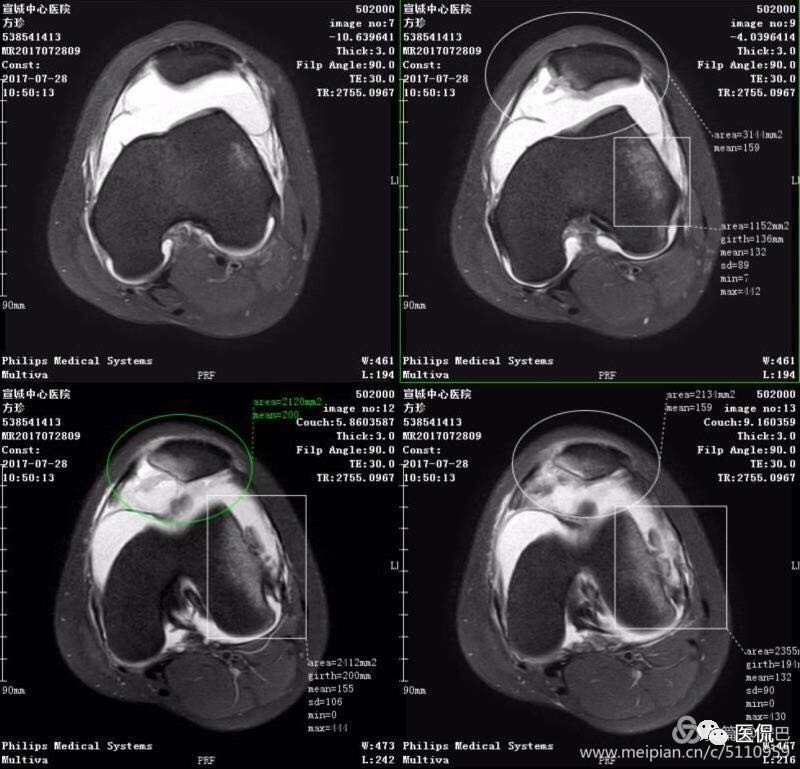

1、单液-液平面:上层呈短T1、长T2信号、T2压脂像低信号、Pd像呈高信号;下层呈中等T1、T2信号、T2压脂像和Pd像呈较高信号。

2、双夜-液平面:上层呈短T1、长T2高信号、T2压脂像低信号、Pd像呈高信号;中层呈长T1、长T2信号、T2压脂像和Pd像呈较高信号;下层呈中等T1、T2信号、T2压脂像和Pd像呈较高信号。

3、多液-液平面:最上层呈无信号区;上层呈短T1、长T2高信号、T2压脂像低信号、Pd像呈高信号;中层呈长T1、长T2信号、T2压脂像和Pd像呈较高信号;下层呈中等T1、T2信号、T2压脂像和Pd像呈较高信号。

2、显示关节囊内骨折、软骨骨折、骨挫伤。

3、同时又能判断交叉韧带、侧副韧带、肌腱以及半月板的损伤。